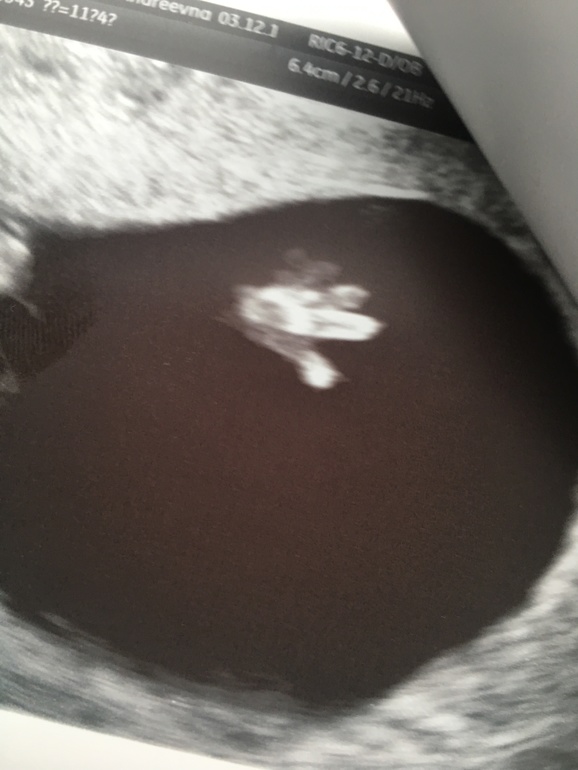

Всё о нашей беременности11+4, все все соответствует норме!

Мозг, ручки, нос кость, воротниковое пространство!я попала к чудо-доктору! Мадан Карнелия. Это благодать! Прием длился 1.20! Узи минут 30. Профессионализм видно сразу, уходили и были так ей благодарны!

Тадааам у нас девушка!!

Сказали что стрелочки не видно, а видно два лепестка и дали 70% что девочка растет!

Это фото: мояяя прелееесть))))лапти скрестила свои)

РУЧКА! Пап, дай пять